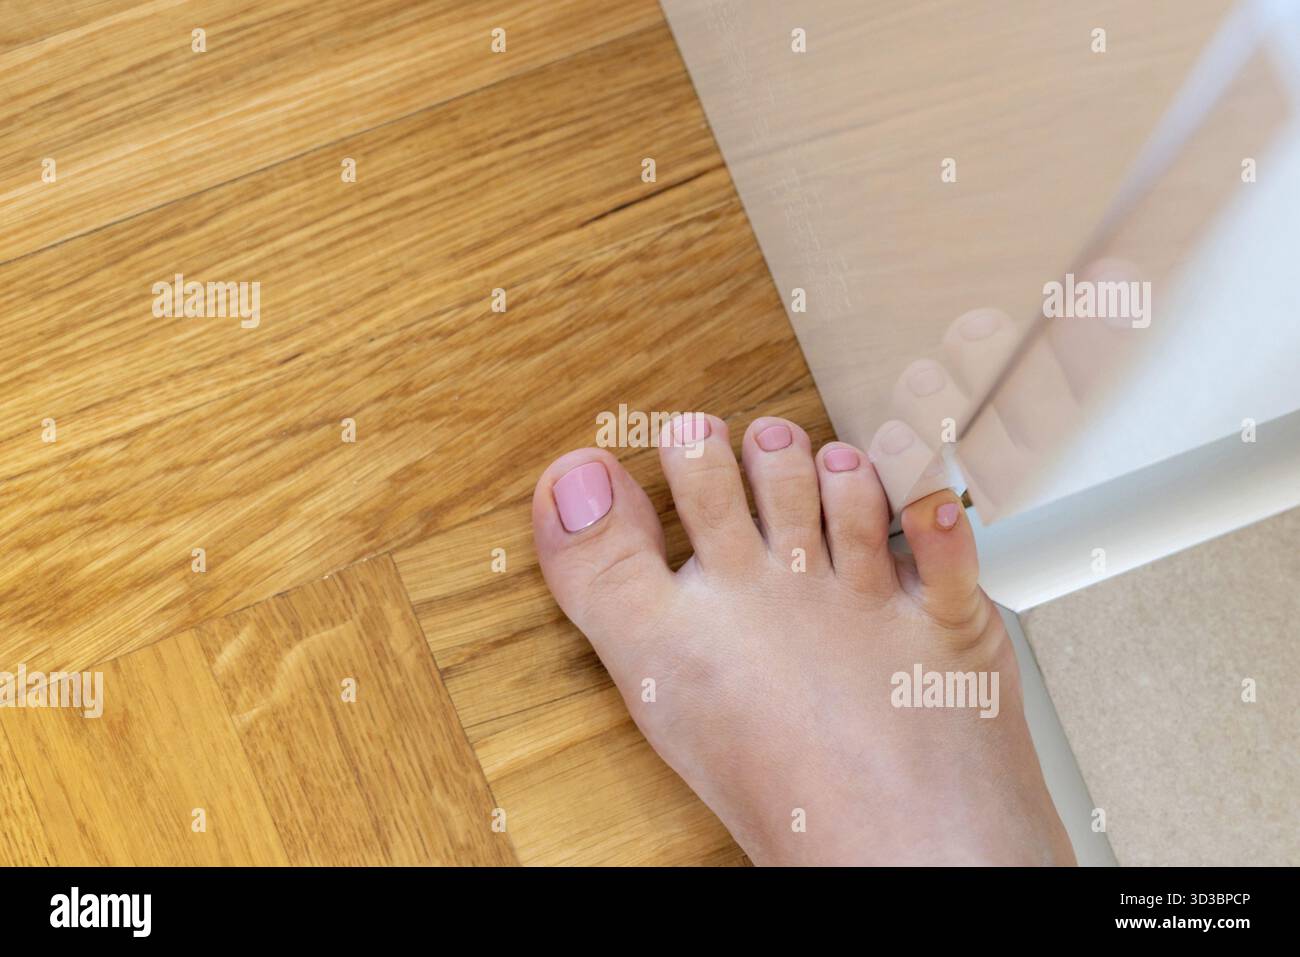

RF2XEDCP0–Frau schlug mit dem kleinen Zeh auf die Möbel. Zwischenfall zu Hause. Verletzung des kleinen Fingers des Fußes